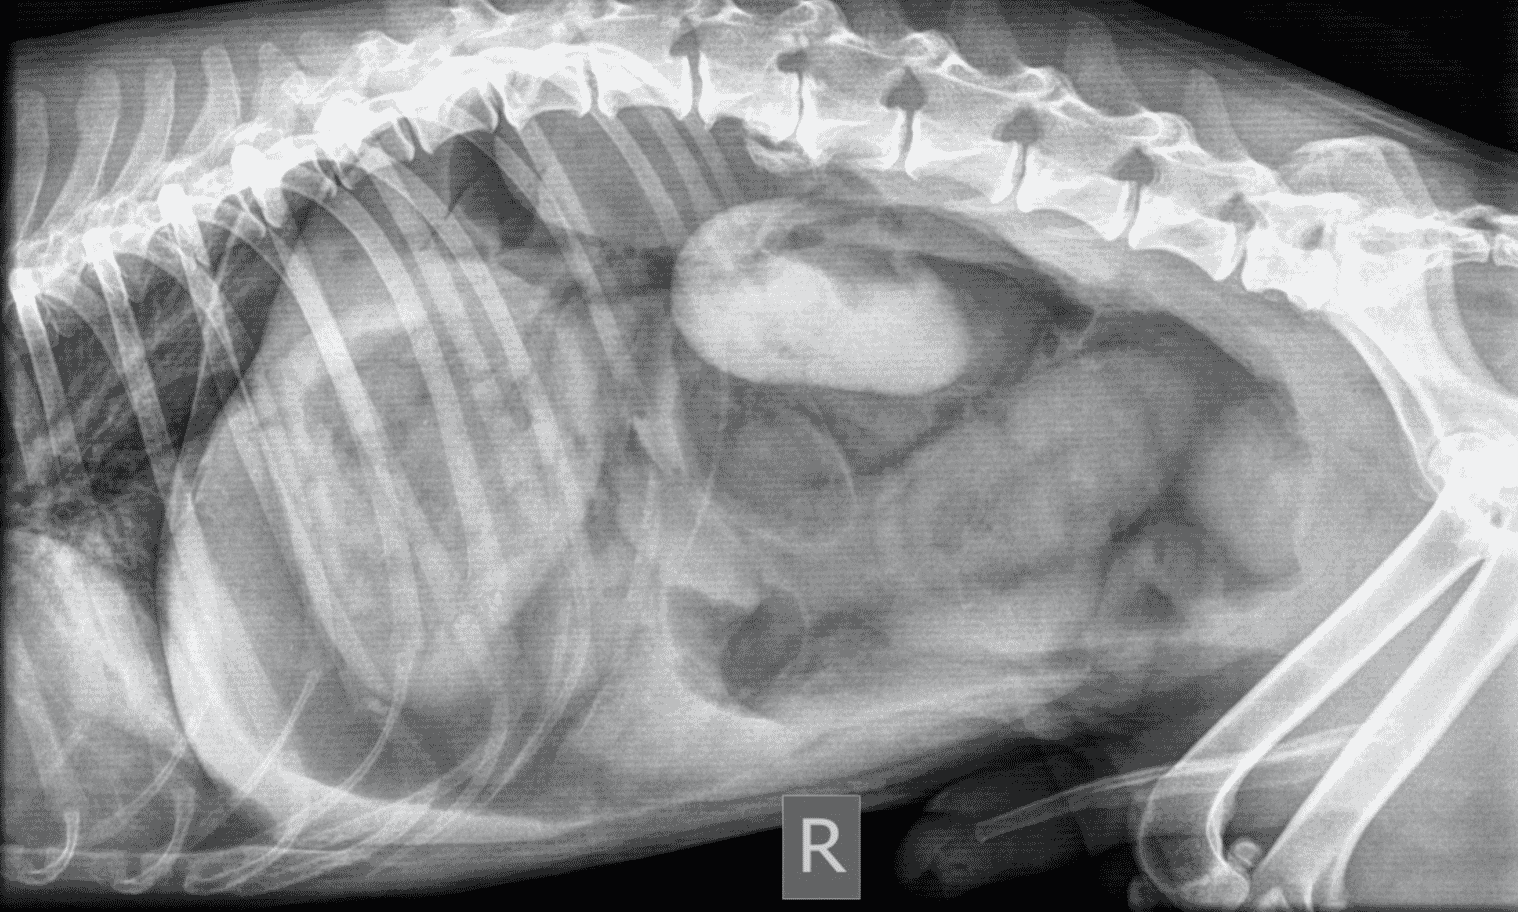

Proximal duodenal and gastric outflow obstruction can cause persistent vomiting with low serum Na, Cl and K; these electrolyte changes should be considered very suspicious even in the absence of imaging findings for obstruction. Abdominal radiographs should include orthogonal views (a right lateral and a ventro-dorsal or dorso-ventral image). Classic radiographic signs for surgical disease can include the “double bubble” for GDV ( Figure 1), two distinct populations of small intestine with obstruction (small and large diameter gut evident with, for example, intussusception, intestinal mass or foreign body; Figure 2) or free abdominal gas with a lack of serosal detail with septic peritonitis. Free abdominal gas can be very obvious ( Figure 3) but a more subtle pneumoperitoneum is best recognised using a horizontal beam radiograph with the patient in lateral recumbency ( Figure 4). Of course, a lack of radiographic changes does not fully exclude a gastrointestinal emergency and abdominal ultrasound can help to identify the problem or guide further diagnostics (eg abdominocentesis of free abdominal fluid). Septic peritonitis due to intestinal leakage will result in an effusion with cytological identification of neutrophils and/or bacteria. If intracellular bacteria can’t be definitively identified but there remains a concern for septic peritonitis, glucose and lactate assessment can be helpful.